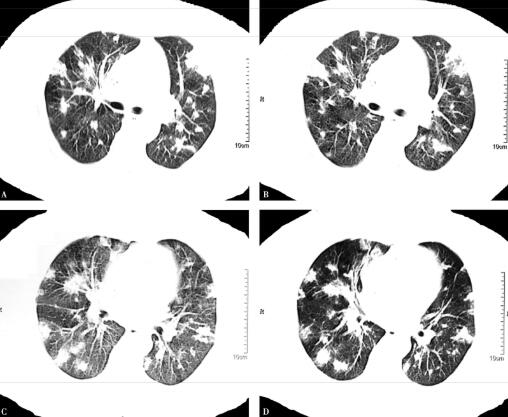

4.胸部CT:

双肺多发结节影、斑片影(图1肺窗,图2纵隔窗)。

图1

血气分析提示酸中毒及Ⅰ型呼吸衰竭,说明病情危重。血常规提示白细胞总数、中性粒细胞百分比均明显增高,说明感染重,结合患者因透析而留置颈内静脉导管,且导管周围皮肤红肿,现畏寒、高热,伴感染性休克等表现,综合分析,更加考虑是导管相关性败血症,进一步确诊需要血培养及导管尖端病菌培养的结果。目前病原学尚不明确,但是根据多年临床经验,糖尿病患者,免疫功能低下,易于感染金黄色葡萄球菌,并且该病菌在导管相关性血流感染的致病菌中占有重要地位,所以金黄色葡萄球菌致病的可能性大。这时胸部影像学提示双肺多发结节影、斑片影,这又是金黄色葡萄球菌感染的“经典”影像。所以目前考虑致病菌是金黄色葡萄球菌可能性极大。进一步的处理应是立即选择合适的抗感染药物进行治疗。